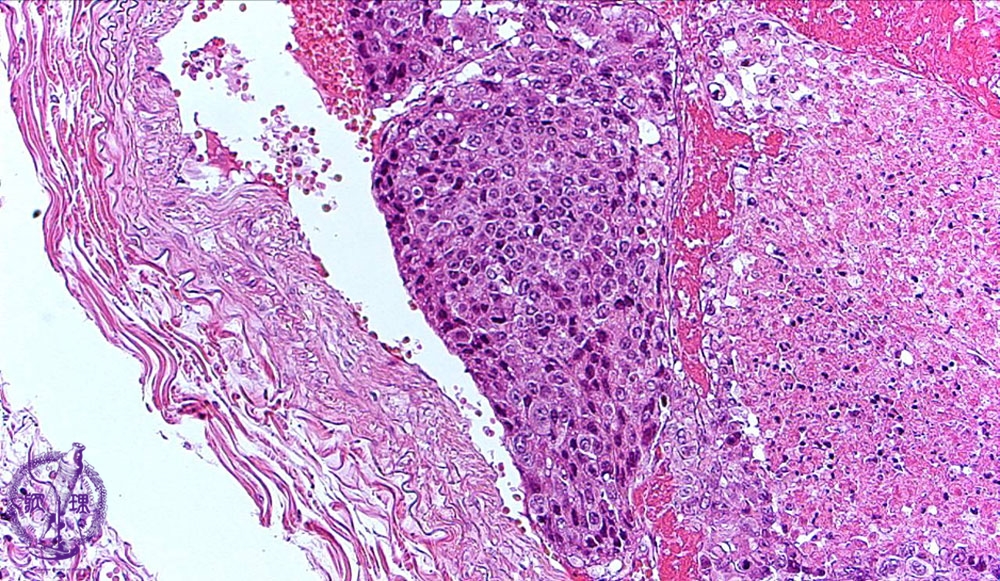

- 5.Lung, Pleura

- (20)Metastatic lung tumor

Microscopic view (HE stain, medium power view): Tumor embolus consists of poorly differentiated hepatocellular carcinoma with coagulative necrosis. On the right side of the tumor, necrosis is seen. In other areas, well differentiated hepatocellular carcinoma is seen.

Click the image to see the enlarged image.